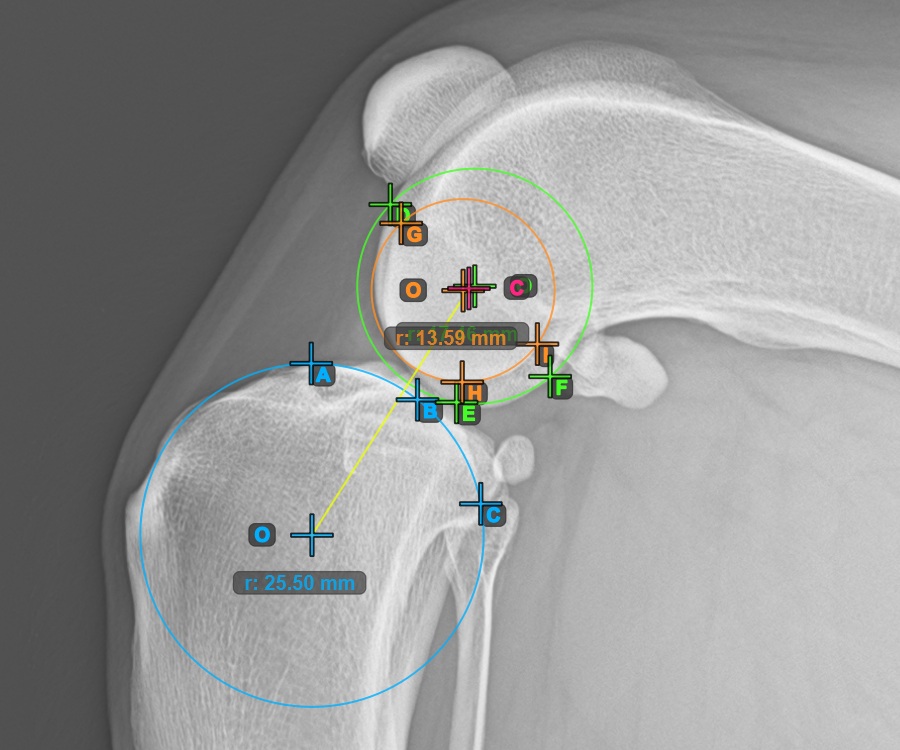

Continue by marking the three points on the articular surface of the first Condylus Femoris.

Mark the three points on the main condylus of the femoral bone (Condylus Femoris). Regardless of the order, make sure to mark the most cranial point, the most caudal point and the midpoint of the Condylus Femoris. A circle will be automatically constructed based on the three placed points.

The image below represents a typical placement of the three points on the first Condylus Femoris.